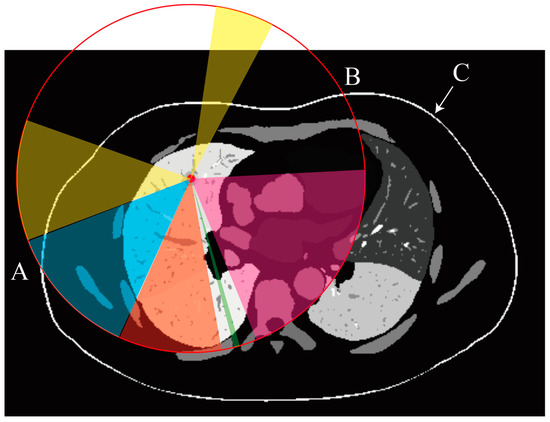

- a.

- Illumination Map Generation and RGB Projection

- b.

- Region Segmentation and Expert Annotation